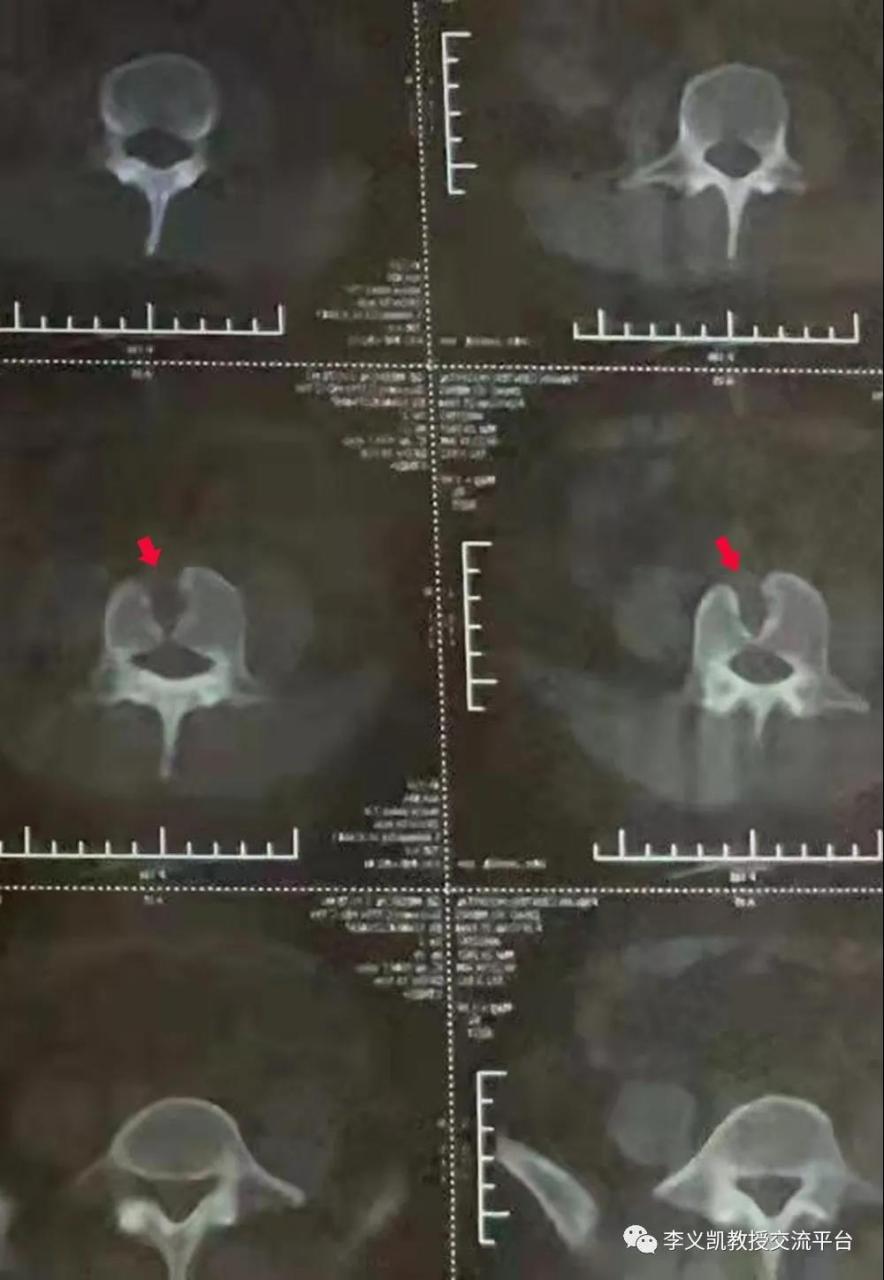

第四腰椎的蝴蝶椎 转发同行照片,本例患者为第四腰椎的蝶形椎,因先天

图片尺寸884x1280